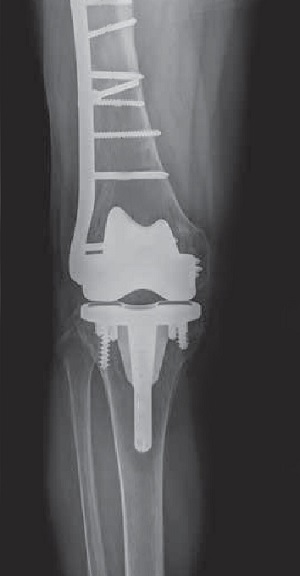

• Periprosthetic Knee Fracture Fixation

Periprosthetic Knee Fracture Fixation

Periprosthetic knee fracture fixation is a procedure performed to stabilize a fracture that occurs in the bone present...